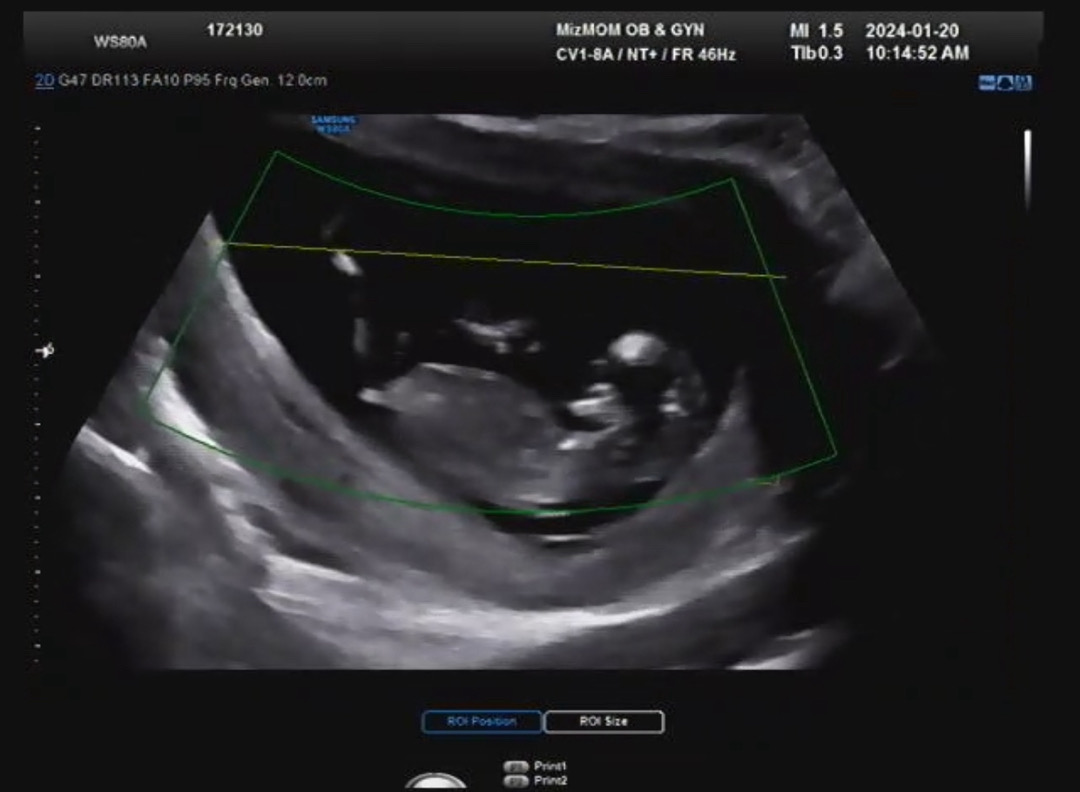

12주 0일차 각도법 봐주세용~~

이 시기에는 모른다고 하시던데 딸일까요 아들일까용???

저게 생식기라면 공쥬여